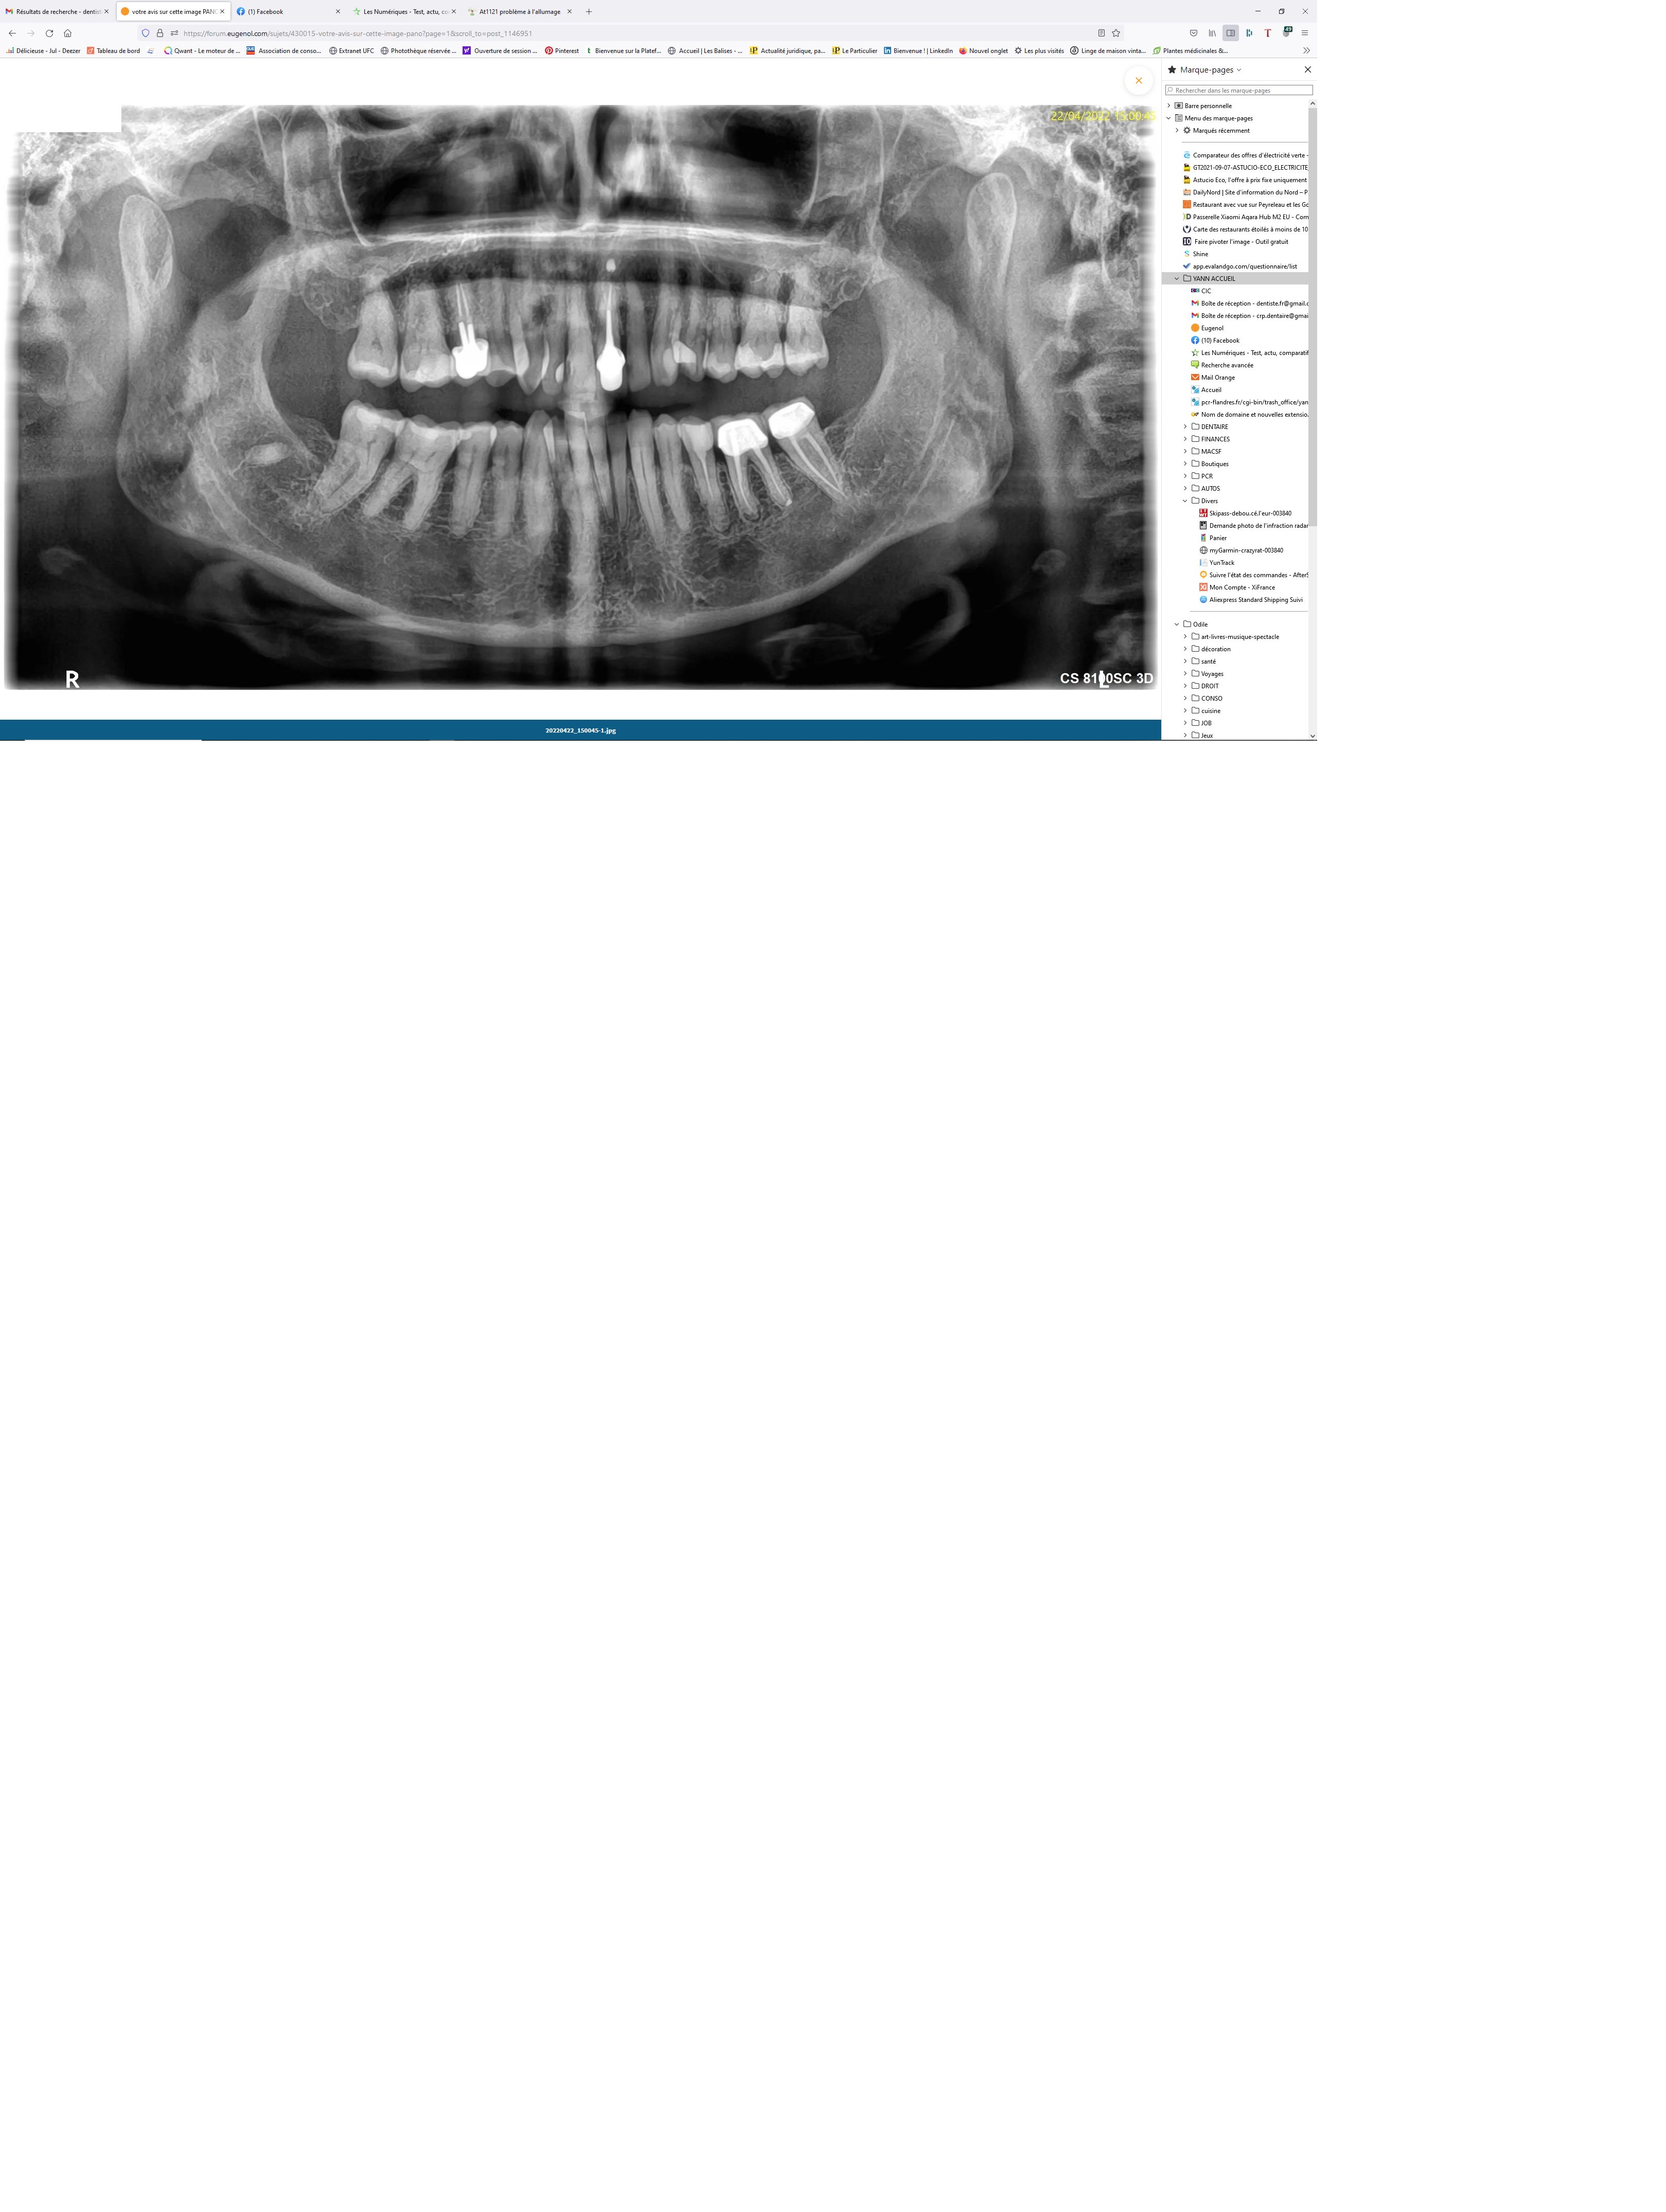

votre avis sur cette image PANO

La patiente que je n'ai vue qu'une fois

me dit avoir consulté en urgence à Biarritz, et le dentiste lui aurait signalé un "abcès en formation"

rien en bouche, j'ai donc réclamé la PANO déjà faite dans le sud Ouest

je suppose donc 13-12

pour moi résorption externe sur 2 dents

et pour vous ?

diagnostic et Plan de traitement ?

tiens je viens de voir que c'est une machine 3D

=> dommage ...

Faudrait faire une rétro de 11 et 12 pour être certain.

Je pense qu’il parlait de 35 et 36.

13-12 , voulais-je dire

Pour “l’image” sur 13-12 ?

Je pense que c’est un artéfact… donc faire une rétro pour confirmer.

Si c’est vraiment des résorptions externes, vu la localisation, j’ai peu d’espoir.

Préparer le davier et 2 implants.

Pour moi 35 36.

+1 avec Cyber pour 12/13 .

ça a l'air moche, à confirmer par une rétro.

A confirmer avec rétro pour 12/13 mais moi aussi je sens juste l'artefact.

L'élargissement desmodontal sur 35/36 est plus cohérent avec l'info donnée par le patient.

L'idéal serait d'appeler le praticien.

Pour moi surveillance et abstention si pas de symptômes. Retraitement envisageable.

j'ai eu un cas similaire il y a quelques années, résorption radiculaires suite à un traumas , j'ai prolongé la "vie" de la dent par endo mais quelques années plus tard il a fallu extraire.